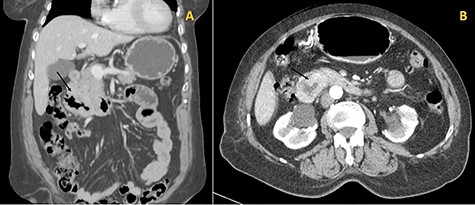

During the hospital stay, an imaging workup was carried out while awaiting the histological diagnosis and the patient had a thoracic, abdominal and pelvic CT done (Fig. 2A and B).

(A) Coronal cut of the abdomen on CT showing the third portion of the duodenum visibly thickened (arrow); (B) Arterial phase showing the circumferential involvement of D3 (arrow).

It described an almost circumferential thickening of the second and third duodenal portions consistent with the lesion described in the endoscopy, extended for 4 cm, with 12 mm of width, and several perilesional adenopathies, the largest measuring 9 mm.